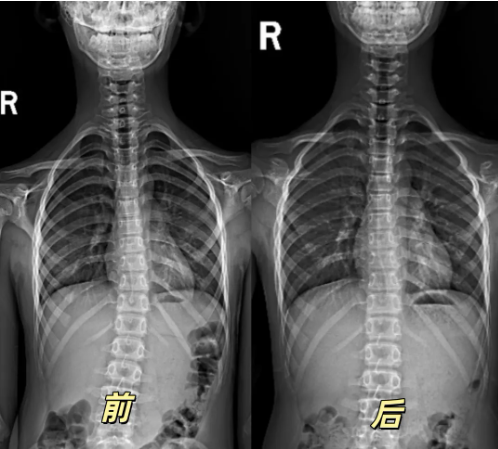

在接诊的案例中,一位11岁9个月的患儿,来就诊时左肩高右肩低,胸段胸段脊柱向左凸了约 16°。针对这一情况,北关院区康复科团队为其制定了详细的康复方案,采用多种治疗手段。经过3个月的不懈努力,肩膀高度已恢复一致,整体姿态得到明显改善。

还有个12岁的孩子,因为驼背已经半年来就诊,来院时不仅驼背,还伴有脖子往前伸、高低肩的问题,检查后确诊为脊柱侧弯。西关院区儿童康复科结合孩子的具体情况,制定了专业化的个体化训练方案。仅仅10天的时间,孩子脖子前伸、驼背、高低肩的情况明显好转,脊柱状态也一天比一天好。